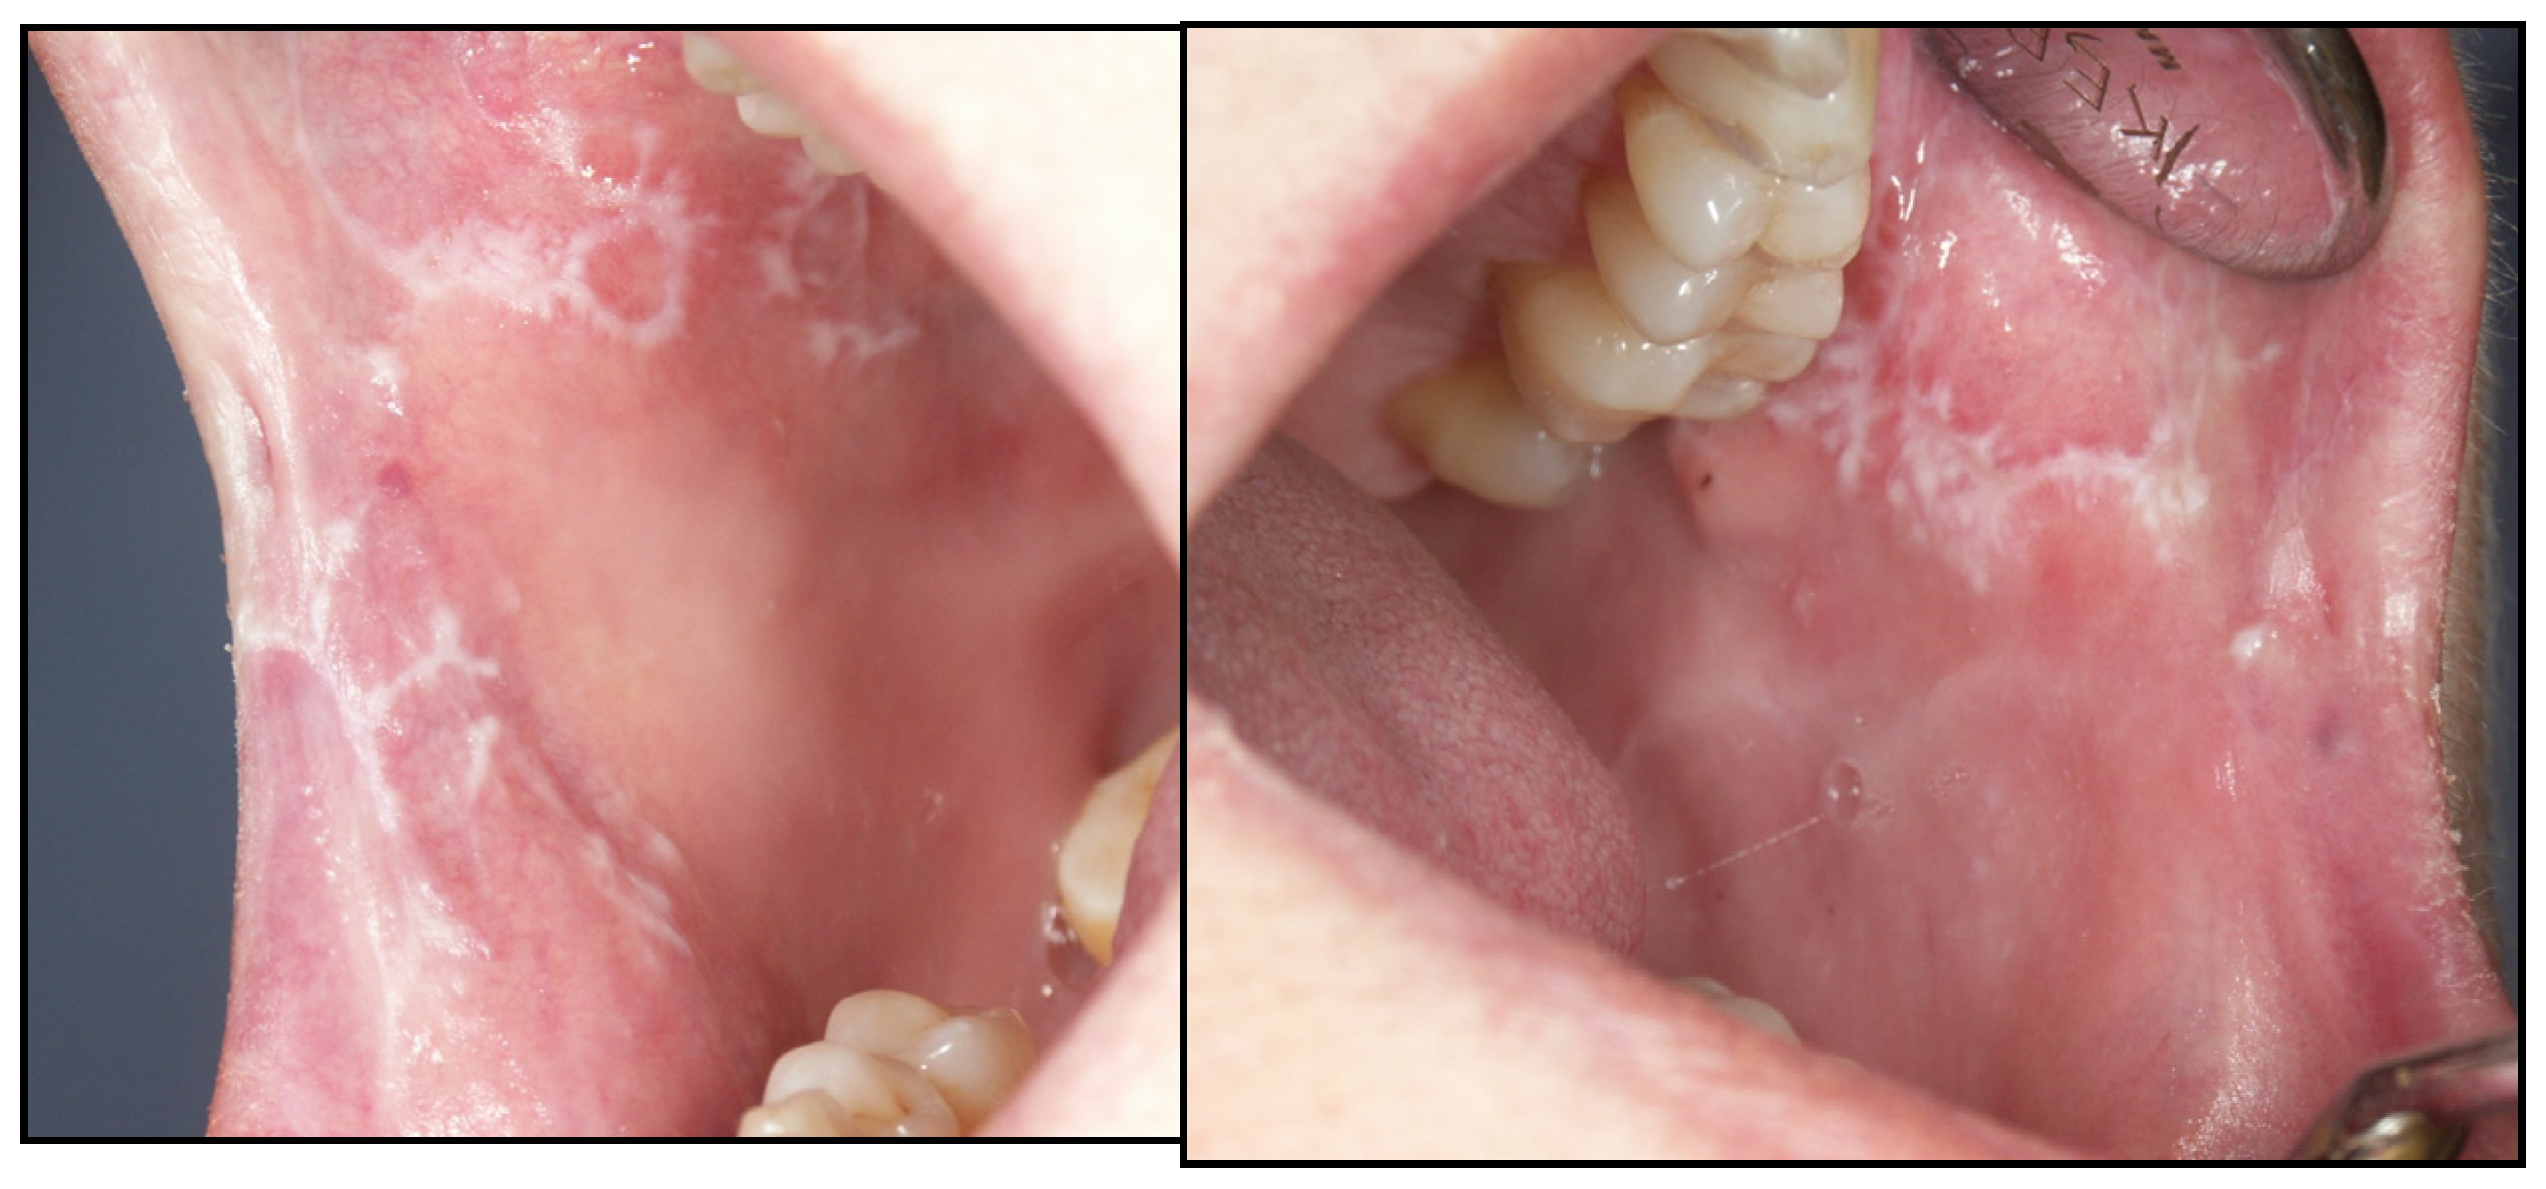

Appendix A. Clinical Presentation of OPMD

General Principles of Treatment of the Main OPMDs

- González-Moles, M.Á.; Warnakulasuriya, S.; González-Ruiz, I.; González-Ruiz, L.; Ayén, Á.; Lenouvel, D.; Ruiz-Ávila, I.; Ramos-García, P. Worldwide prevalence of oral lichen planus: A systematic review and meta-analysis. Oral Dis. 2021, 27, 813–828. [Google Scholar] [CrossRef]

- González-Moles, M.Á.; Ruiz-Ávila, I.; González-Ruiz, L.; Ayén, Á.; Gil-Montoya, J.A.; Ramos-García, P. Malignant transformation risk of oral lichen planus: A systematic review and comprehensive meta-analysis. Oral Oncol. 2019, 96, 121–130. [Google Scholar] [CrossRef]

- Ramos-García, P.; González-Moles, M.Á.; Warnakulasuriya, S. Oral cancer development in lichen planus and related conditions-3.0 evidence level: A systematic review of systematic reviews. Oral Dis. 2021, 27, 1919–1935. [Google Scholar] [CrossRef]

- González-Moles, M.Á.; Ramos-García, P.; Warnakulasuriya, S. An appraisal of highest quality studies reporting malignant transformation of oral lichen planus based on a systematic review. Oral Dis. 2021, 27, 1908–1918. [Google Scholar] [CrossRef]

- González-Moles, M.Á.; Ramos-García, P. Oral lichen planus and related lesions. What should we accept based on the available evidence? Oral Dis. 2022. [Google Scholar] [CrossRef]